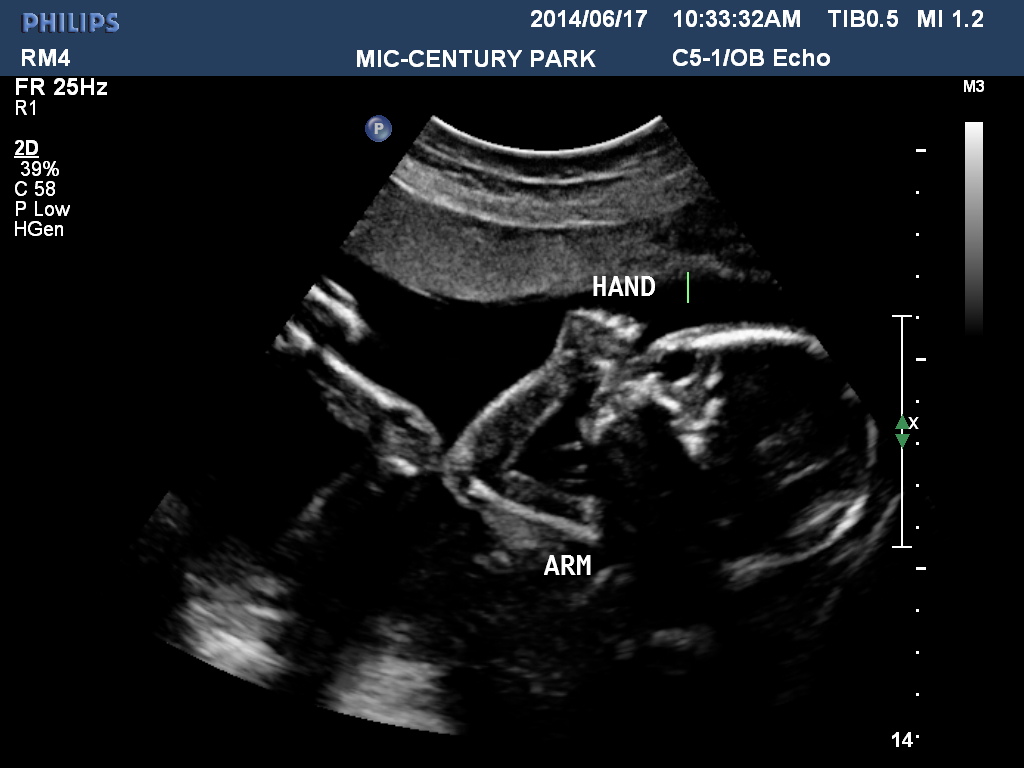

I went for my anatomy scan at 20 w 4 d. I did not ask the tech then about the gender however now i am very anxious! I haven't got that many pics but heres one. Not sure if it will be clear enough.Attachment 19533Attachment 19534